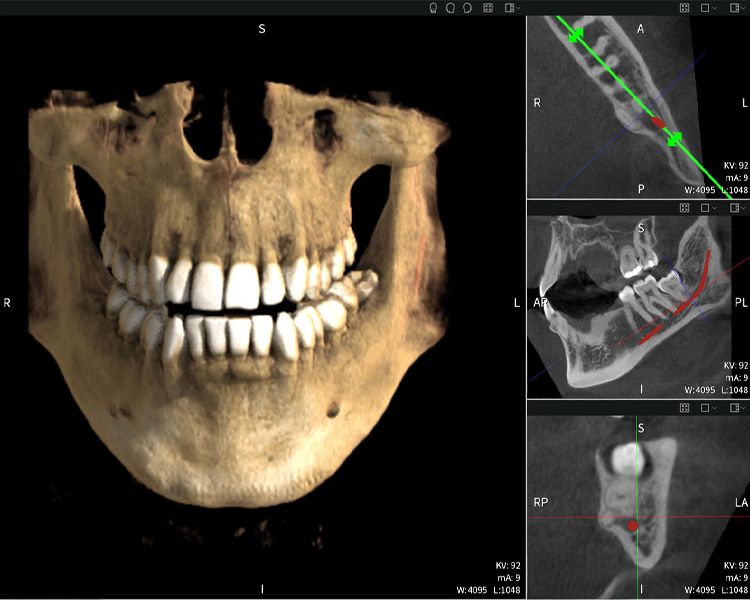

Nachstehend finden Sie einen Fall von Dr. med. dent. Oliver A. Centrella, in dem die CBCT-Aufnahmen mit Seethrough Max entscheidende Informationen zur komplexen Anatomie sowie zur kritischen Beziehung zwischen den Weisheitszähnen und dem Nervus alveolaris inferior lieferten. Bei diesem Fall besteht eine Indikation zur chirurgischen Entfernung der Weisheitszähne.

• Oben links: Axiale Schnittansicht des linken Unterkiefers (Region 38) mit Darstellung des Nervus alveolaris inferior (rot) in unmittelbarer Nähe zu den Wurzeln des Zahns 38.

• Oben rechts: 3D-Rekonstruktion des gesamten Unterkiefers zur Orientierung. Der rot markierte Nervus alveolaris inferior verdeutlicht seine Lage im Kieferknochen.

• Unten links: Sagittale Ansicht des Unterkiefers (Region 38), die die enge räumliche Beziehung zwischen den Wurzeln und dem Nervenkanal verdeutlicht.

• Unten rechts: Koronale Ansicht des Unterkiefers (Region 38) entscheidend für die Beurteilung der räumlichen Lage der Wurzeln zum Nerven.

Abbildungen b–d zeigen verschiedene Ansichten einer 3D-Rekonstruktion des Unterkiefers und bieten eine umfassende Übersicht über die Anatomie des Unterkiefers, die Lage der Nerven im Verhältnis zu den Zähnen und ermöglichen die Beurteilung der Zahnsymmetrie und Ausrichtung.

Abbildung d zeigt den bereits vorbehandelte Zahn 48, dessen Krone entfernt wurde und dessen Wurzeln nahe am Nerv belassen wurden, was das hohe Risiko einer Nervenschädigung verdeutlicht.